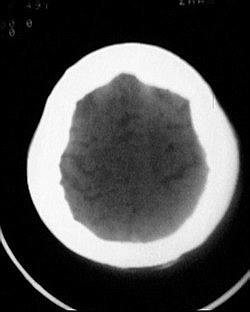

患者/49y/ 女/4年前有脑梗, 现因右侧肢体无力来院做ct扫描 ! 老师们看看这骨头有事吗?钙化点是什么原因呀??

3、“钙化点”是指哪一个呀?是四叠体池左旁的那个吗?那个不好说,可能是感染性病变留下的,我估计临床意义不大,实在不放心做个增强看看有没有其它什么东东。

1.颅骨对称性、形态规整性增厚,应属发育异常。四叠体池左后侧单发点状钙化,无其他阳性表现,多属正常,不需要过多关注。

2.双侧基底节区域多发性梗塞灶。

除了以上大家关注到的,我发现左侧鼓室、鼓窦扩大有骨质破坏,考虑有慢性中耳炎肉芽肿形成

不知脑囊虫病(单发)能否排除?临床病史及实验室检查结果?

“泛发性骨皮质增厚症,又称骨内膜增生症(endosteal hyperostosis):分为常染色体隐性遗传性疾病(van buchem)和常染色体显性遗传性骨硬化症(worth病)。后者更少见,亦较轻。两者的病理上均为骨内膜 成熟的板状新生骨形成,髓腔变窄。颅骨、颅底骨 、下颌骨,肋骨、四肢骨及骨盆骨、脊柱均可见骨内膜增生,髓腔变窄或消失,但骨外径不加大,骨骺不累及。”

本例的确应该这个病。建议楼主检查病人其他部位有无类似表现,以便确诊。